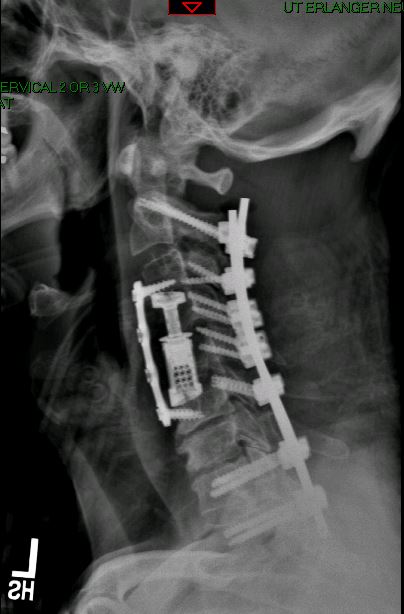

Imaging Gallery

Before & After

Spine Surgery

All imaging is fully de-identified. Patient identifiers removed in compliance with HIPAA.